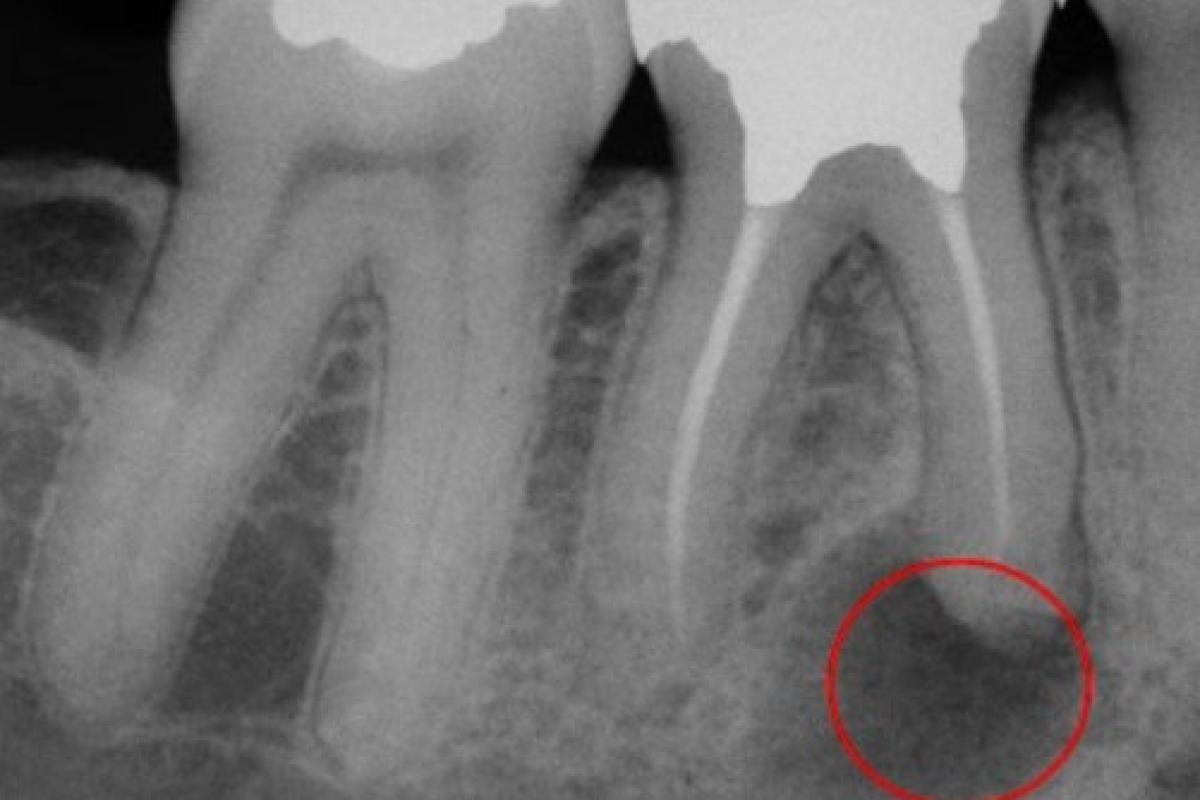

Гранулемы редко превышают 1 см в диаметре. Небольшие гранулемы можно различить только при рентгенологическом исследовании, ортопантомограмме или компьютерной томографии.

- компьютерная томография. На рентгене гранулема выглядит как округлое затемненное пятно с четкими контурами.